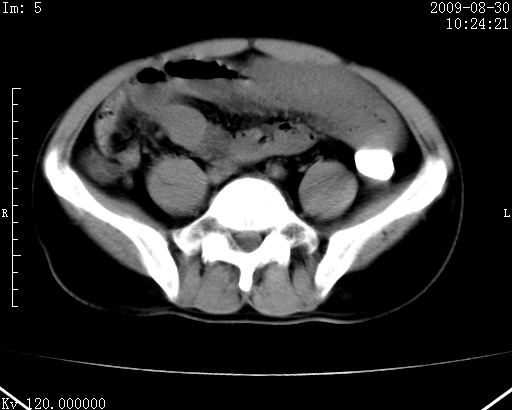

患者唐某,男31岁,已婚,本地务农。

自述入院前两天一次进食较多冷饮之后,出现阵发性上腹部疼痛,次日加剧伴恶心、呕吐,呕吐后症状稍减轻。食欲差。大便每天1-2次,量少,暗红色水样。小便赤。无畏寒、发热、咳嗽等呼吸道症状。无高血压及胃病史。

检查:体温、血压及脉搏正常.皮肤无黄染,浅表无淋巴结肿大。左腹肌紧张,左上腹有压痛,无反跳痛,可触及包块。

生化:钾、钠、氯、钙、ph正常,总胆红素和直接胆红素稍高,空腹血糖稍高。

尿淀粉酶:1256 u/l(正常60-401)。

血常规:wbc 22.4x109/l gr88% ly9.6%其余基本正常。

胃镜:急性胃炎。立位腹平片:未见异常。

下面是ct平扫,降结肠内是对比剂。

术前影像诊断:上段空肠急性缺血性坏死并腹水。建议手术治疗。

术中见上段空肠约70cm长范围坏死,从屈氏韧带远端约10cm处开始。坏死肠管肿胀变形变色,管壁明显环形增厚,部分聚成大肿块,无扭转和套叠。肠系膜上动脉分支内广泛泥沙状血栓。肠切除。

临床诊断:肠系膜上动脉梗塞并急性肠坏死。

开始时我们科也有人认为是套叠,最后统一意见,不考虑肠套。我们看到的“靶征”,“晕圈征”,“双圈征”实际上只是单根肠管的横断面。坏死肿胀后肠壁各层的密度不一样。

左侧腹小肠腔管壁明显增厚,部分内示靶征,走行异常,部分肠系膜绳样改变,肝包膜下及肠间较多液体密度,然梗阻近端肠腔积气不明显。

考虑;肠扭曲伴肠坏死。

有结果了,回顾分析,套叠只会在局部出现同心圆征,不会很长一段肠管都有,还是水肿坏死。